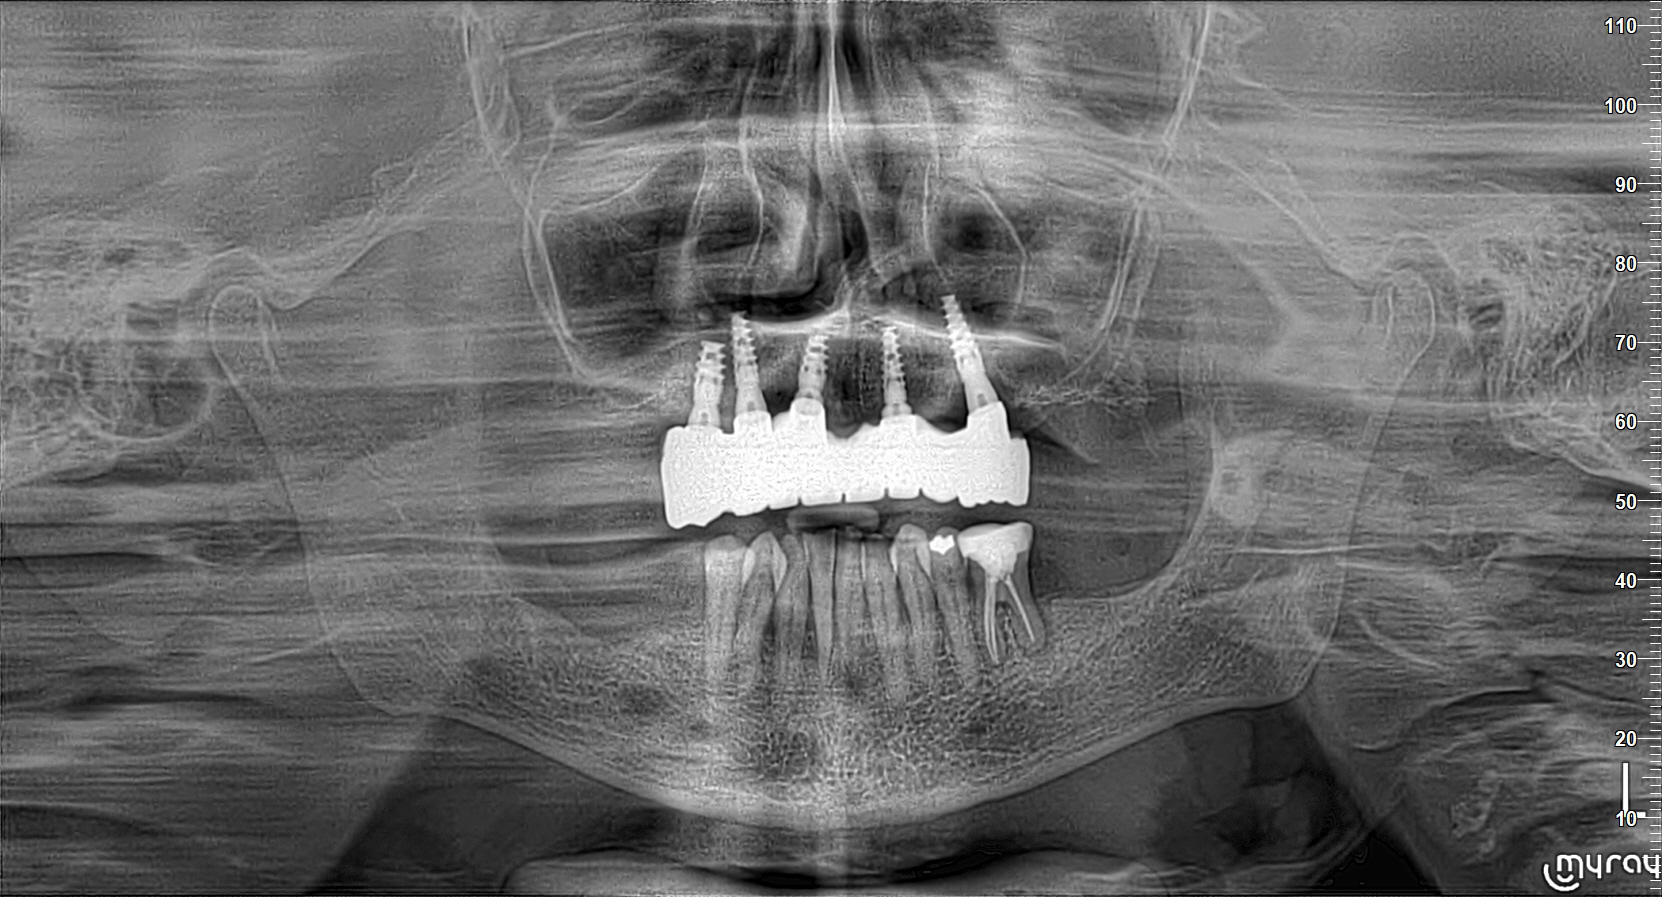

Due to a severely atrophic maxilla, all remaining teeth were extracted under local anesthesia. Immediately following extraction, five DSI conical implants were placed in positions 15, 13, 11, 21, and 24. Cover screws were inserted, and a complete denture was provided as a temporary solution one week post-surgery.

After six months of osseointegration, the cover screws were replaced with DSI multi-unit abutments (MUA) 1.6, and healing caps were inserted. One week after the second-stage surgery, digital impressions were taken at the MUA level using DSI scan bodies and a Dentsply Sirona Primescan intraoral scanner.